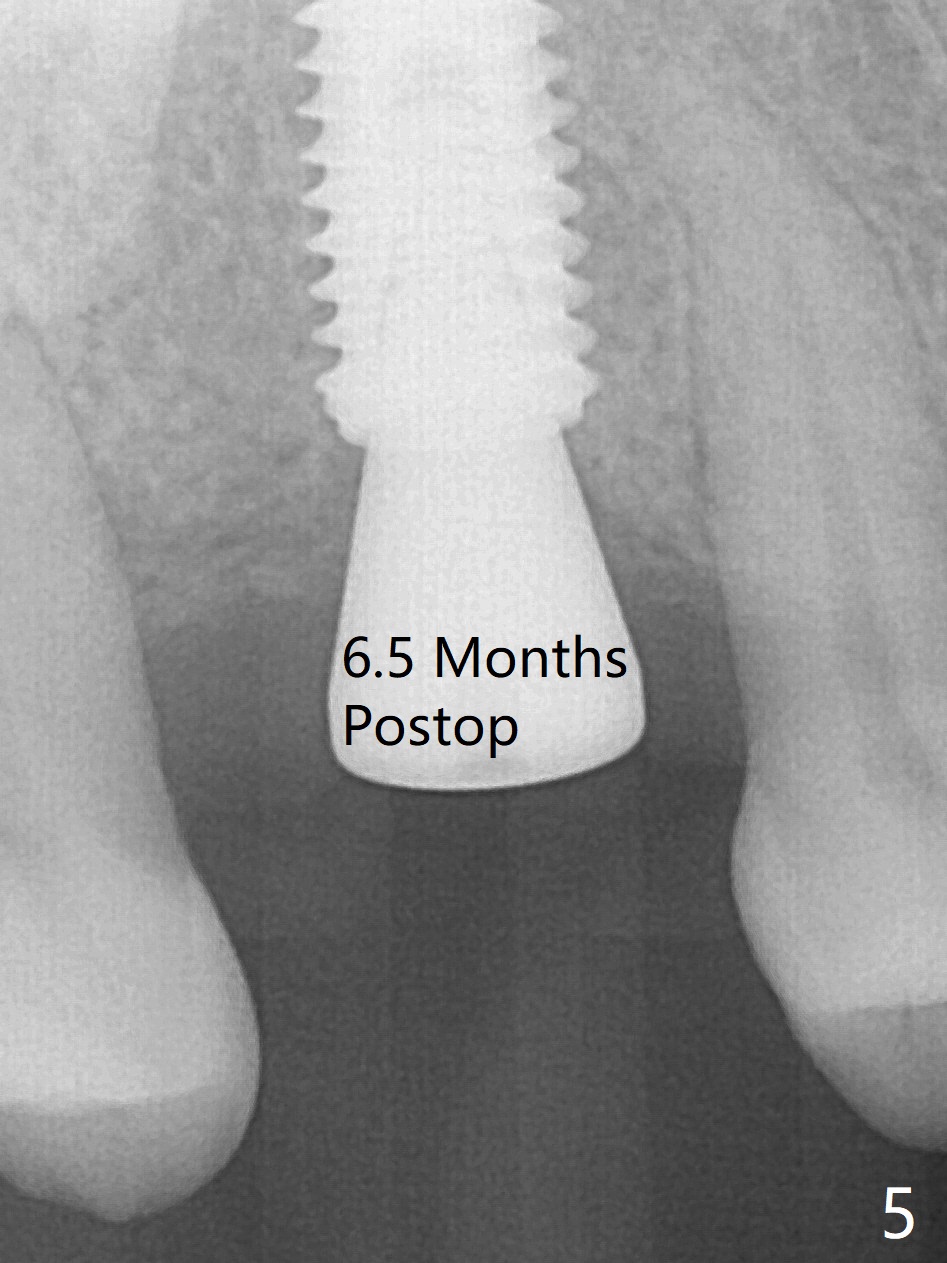

In order to place a 5x11.5 mm implant at #3 completely in depth, the preop CBCT coronal section is reanalyzed (Fig.1). It appears that extra 1 mm osteotomy does not perforate the sinus floor. After finishing osteotomy according to the guide plan, a 3.5x13 mm drill is used ~ .5 mm shy of the depth without sign of sinus membrane leakage. The implant is placed with apparently satisfactory depth, but it is quite close to the curved root tip of the neighboring tooth (Fig.2,3). In fact postop CBCT shows that there is a clearance (Fig.4). To prevent the similar event in the future, the implant should be designed slightly distal. The postop CBCT also shows that the extra depth is not necessary (Fig.4 *); it seems that the inherent 1.2 mm drill tip is sufficient for the depth overprep. The implant is stable for impression 6.5 months postop (Fig.5), whereas that placed immediately free hand is unstable 7.5 months postop. Two weeks later, the patient experiences severe pain when the abutment is being retightened. The crown at #3 is delivered 3 months later (9 months postop). It appears that the bone heals slow in this patient.